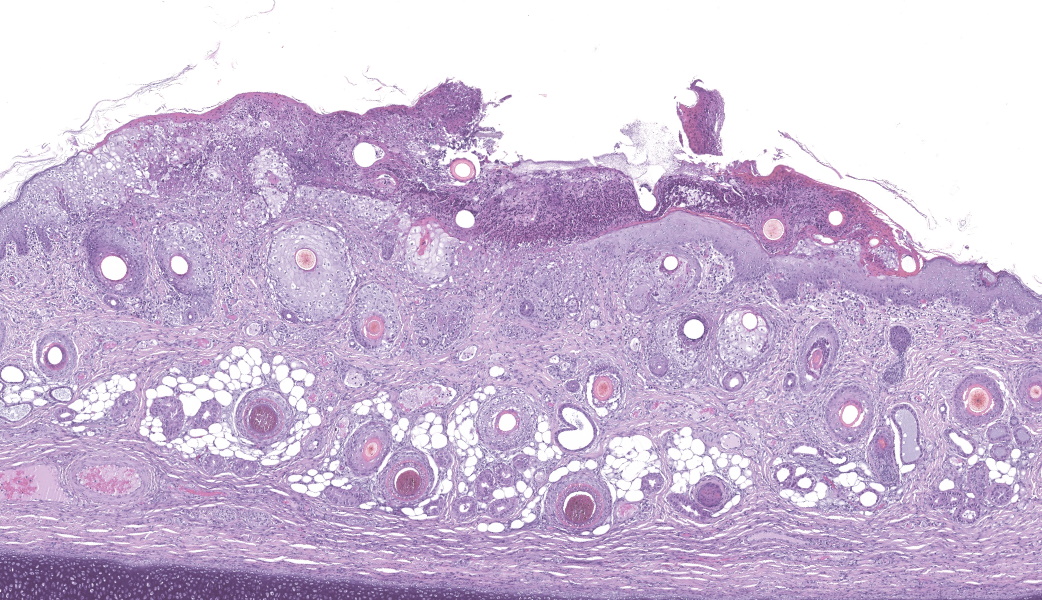

Haired skin (ear, prepuce, and inguinal area): affecting 20% of the evaluated section there is a proliferative and necrotizing process that mainly affects the epidermis. The epidermis and hair follicle epithelium show the following features: stratum corneum with diffuse mild compact hyperkeratotic orthokeratosis with multifocally serocellular crusts composed by cellular debris, degenerated keratin, degenerated neutrophils, and multiple superficial coccoid bacterial colonies (secondary contamination). Also, stratum spinosum shows multifocal marked thickening (acanthosis), and numerous keratinocytes display ballooning degeneration and intracytoplasmic perinuclear 2-5 ?m eosinophilic inclusion bodies. Multifocally, in the most affected areas, there is marked neutrophilic exocytosis, and numerous keratinocytes lost intercellular connections and undergo lytic necrosis. Superficial and mid dermis show perivascular to diffuse, moderate to severe inflammatory infiltrates composed by viable and degenerated neutrophils, macrophages, and lesser numbers of lymphocytes and plasma cells. Significant lesions were not seen in the hypodermis.Contributor's Morphologic Diagnoses:

Morphologic diagnosis: Haired skin; severe, subacute, proliferative, necrotizing, and crusting dermatitis with intracytoplasmic eosinophilic inclusion bodies. Etiologic diagnosis: Poxviral dermatitis. Etiology: Swine poxvirus.Contributor's Comment:

The typical histological features of SwPV infection comprises hydropic degeneration of keratinocytes of the epidermal stratum spinosum and follicular epithelium during the papular phase. As a result, thickening of the epidermis due to mild spongiosis can be observed; however, epidermal hyperplasia caused by SwPV is usually less prominent than that caused by the other poxviruses.7 Other finding are eosinophilic inclusion bodies in the cytoplasm of infected cells.7 Regarding inflammation, the damage caused by virus replication on keratinocytes causes recruitment of neutrophils, eosinophils, lymphocytes and histiocytes, forming intraepithelial pustules, as well as in the superficial and mid-dermis.4,6,7

Haired skin: Dermatitis, necrotizing and proliferative, subacute, multifocal, severe, with ballooning degeneration and intracytoplasmic viral inclusions.

This was a truly phenomenal case of congenital swinepox, complete with clear viral inclusions and all the classic histologic features of the disease. The JPC extends sincere gratitude to the contributor of this case for providing such an exceptional example of this entity for the Wednesday Slide Conference!One of the very first questions posed to conference participants was, “If poxvirus is a dsDNA virus, why are the inclusions cytoplasmic instead of intranuclear?” This is because poxviruses are unique among DNA viruses in that they possess all their own required machinery, including their own DNA-dependent RNA polymerase, to carry out replication and transcription independent of the host cell nucleus.9 Poxviruses can even go so far as to form their own membrane-bound "mini-nuclei" within the cytoplasm, derived from rough endoplasmic reticulum.9 These cytoplasmic sites contain all the components needed for viral DNA replication and protein synthesis. As such, poxviral inclusions will be seen in the cytoplasm of infected keratinocytes instead of in the nucleus.